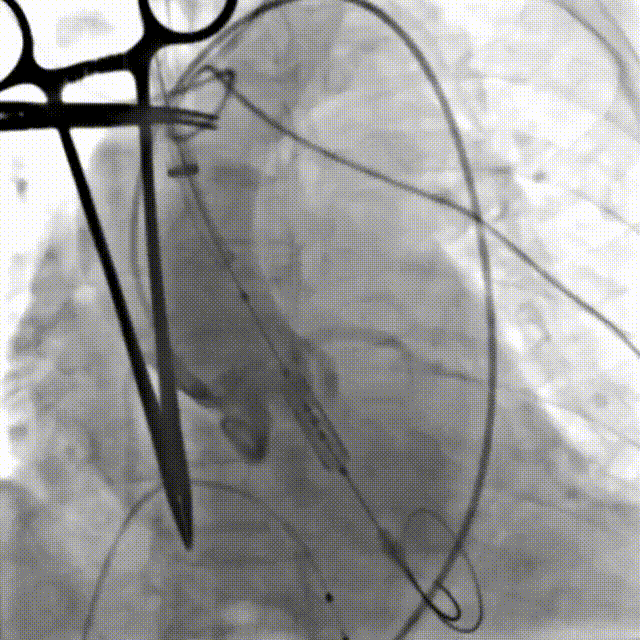

患者全麻后,游离颈动脉建立入路,主动脉根部造影显示主动脉瓣明显钙化伴重度狭窄。直头导丝跨瓣后,测得左心室、主动脉压力分别为180/-7mmHg,84/45mmHg。在180次/分快速心室起搏下,选择18mm球囊进行预扩张。根据术前评估及球囊预扩情况,最终选择23mm Prizvalve®球扩瓣进行植入,主动脉根部造影见轻微主动脉瓣反流,复查左心室、主动脉压力分别为151/1mmHg、150/72mmHg。术后即刻经食道超声心动图评估峰值流速1.4m/s,平均压差4mmHg,瓣口面积约2.1cm²,血流动力学指标理想。

球囊预扩张